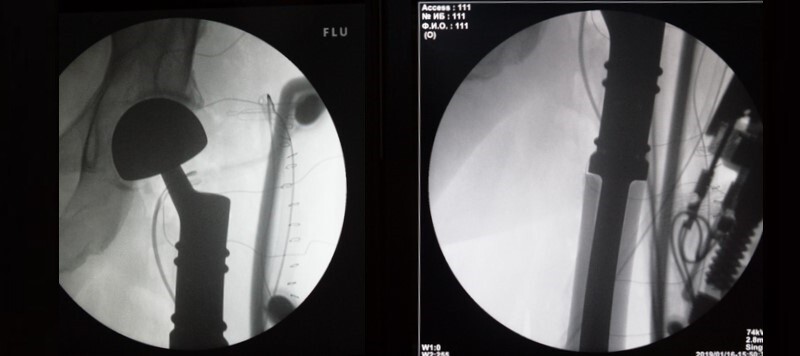

После операции выполняется контрольный снимок эндопротеза в 2-х проекциях: